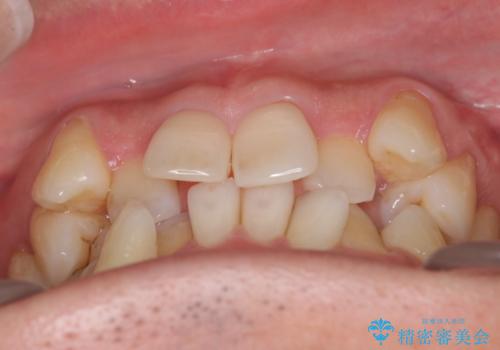

- 治療計画

叢生量が大きいため、上下顎両側4番を抜歯しました。矯正治療による歯肉退縮の著しい悪化もなく、主訴であるガタつきも改善できました。